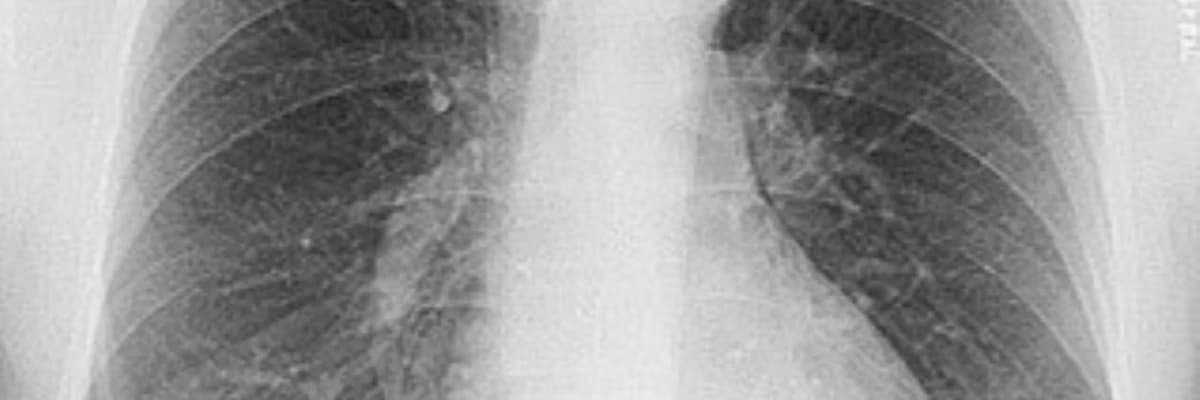

Birincil və ikincil pnevmotoraks - qazların, plevrə havanın yığılması.

Pnevmotoraks, ağciyər sağlamlığına ciddi təsir göstərən və təcili tibbi yanaşma tələb edə bilən bir vəziyyətdir. Tibbi praktikada bu vəziyyət əsasən iki qrupa bölünür: birincil və ikincil pnevmotoraks. Hər iki növün yaranma mexanizmi və risk faktorları bir-birindən fərqlənir.

Bu növ, əsasən hər hansı bir ağciyər xəstəliyi olmayan sağlam şəxslərdə inkişaf edir. Birincil pnevmotoraks, adətən ağciyərlərin səthində yerləşən və bleb adlanan kiçik hava kisələrinin partlaması nəticəsində meydana gəlir. Statistik olaraq, bu vəziyyətə daha çox uzunboylu və arıq kişilərdə rast gəlinir və çox vaxt yaranma səbəbi tam olaraq açıqlana bilmir.

2. İkincil Pnevmotoraks

İkincil pnevmotoraks, əvvəlcədən mövcud olan ağciyər xəstəlikləri və ya patoloji vəziyyətləri olan insanlarda müşahidə edilir. Aşağıdakı xəstəliklər ikincil pnevmotoraks riskini əhəmiyyətli dərəcədə artırır: